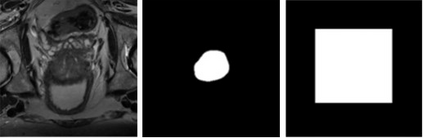

Prostate segmentation from magnetic resonance imaging (MRI) is a challenging task. In recent years, several network architectures have been proposed to automate this process and alleviate the burden of manual annotation. Although the performance of these models has achieved promising results, there is still room for improvement before these models can be used safely and effectively in clinical practice. One of the major challenges in prostate MR image segmentation is the presence of class imbalance in the image labels where the background pixels dominate over the prostate. In the present work we propose a DL-based pipeline for cropping the region around the prostate from MRI images to produce a more balanced distribution of the foreground pixels (prostate) and the background pixels and improve segmentation accuracy. The effect of DL-cropping for improving the segmentation performance compared to standard center-cropping is assessed using five popular DL networks for prostate segmentation, namely U-net, U-net+, Res Unet++, Bridge U-net and Dense U-net. The proposed smart-cropping outperformed the standard center cropping in terms of segmentation accuracy for all the evaluated prostate segmentation networks. In terms of Dice score, the highest improvement was achieved for the U-net+ and ResU-net++ architectures corresponding to 8.9% and 8%, respectively.